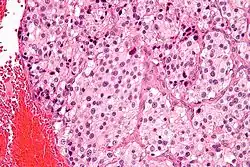

| Micrograph of a carotid body tumor (a type of paraganglioma) | |

On microscopic inspection, the tumor cells are readily recognized. Individual tumor cells are polygonal to oval and are arranged in distinctive cell balls, called Zellballen.[9] These cell balls are separated by fibrovascular stroma and surrounded by sustentacular cells.

By light microscopy, the differential diagnosis includes related neuroendocrine tumors, such as carcinoid tumor, neuroendocrine carcinoma, and medullary carcinoma of the thyroid.

With immunohistochemistry, the chief cells located in the cell balls are positive for chromogranin, synaptophysin, neuron specific enolase, serotonin, neurofilament and Neural cell adhesion molecule; they are S-100 protein negative. The sustentacular cells are S-100 positive and focally positive for glial fibrillary acidic protein. By histochemistry, the paraganglioma cells are argyrophilic, periodic acid Schiff negative, mucicarmine negative, and argentaffin negative.